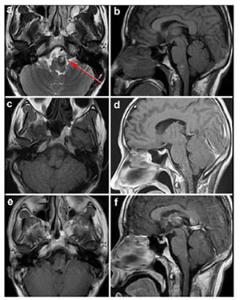

20170712151439 Figure 4 Case 2: Left anterolateral medullary cavernous malformation. Axial T2-weighted (a) and sagital T1-weighted (b) showed the location of the lesion. Axial T1-weighed (c) and enhanced sagittal T1-weighted (d) postoperative within 72 h showed that the lesion was totally resected. Enhanced axial T1-weighted (e) and enhanced sagittal T1-weighted (f) at 5-month postoperative follow-up. Red arrow showed the entry approach (retrosigmoid approach).